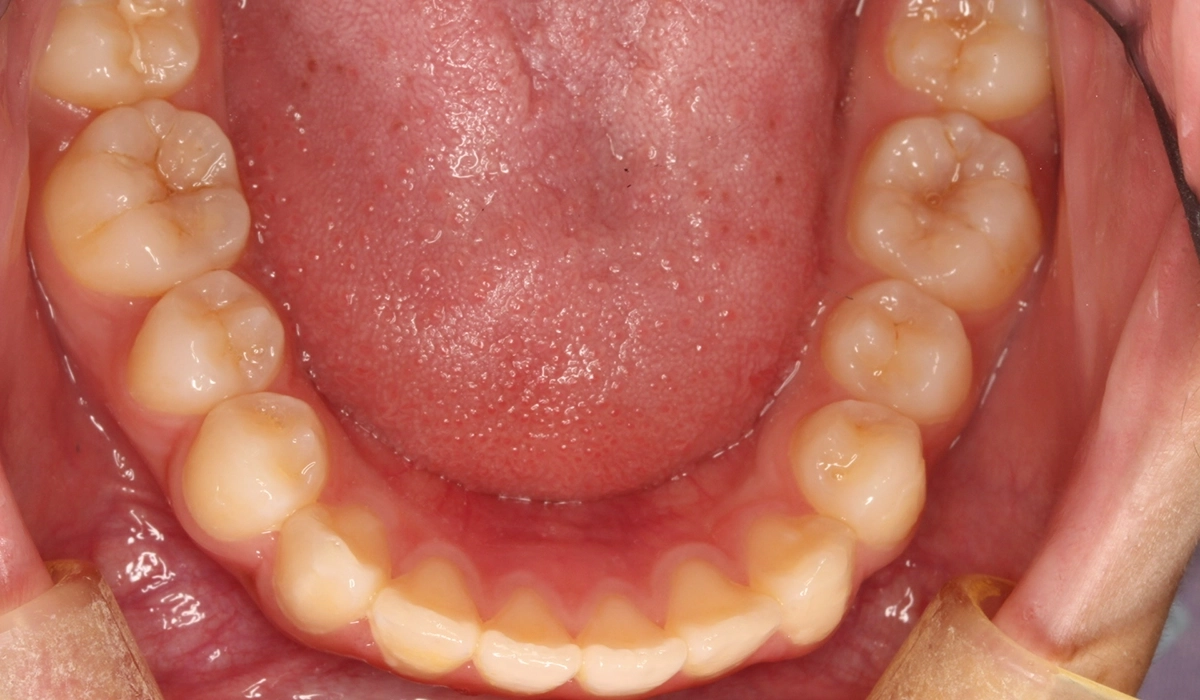

術前:下顎

術後:下顎